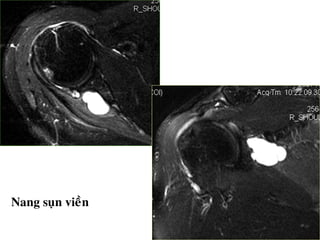

Toån thöông suïn vieàn

- Bình thöôøng, suïn vieàn coù tín hiệu thấp

treân tất cả caùc chuỗi xung.

- Raùch suïn vieàn: bieán daïng suïn vieàn, coù

ñöôøng tín hieäu dòch beân trong suïn vieàn.

- Löu yù bieán theå bình thöôøng cuûa suïn vieàn.

• - MRI thường quy khoù ñaùnh giaù toån thương

suïn vieàn. Toån thương suïn vieàn tröôùc: ñoä nhaïy

44-95% , ñoä ñaëc hieäu 67-86%.

• - MR Arthrography coù ñoä nhaïy 90% vaø ñoä

ñaëc hieäu 95%.

Nang suïn vieàn